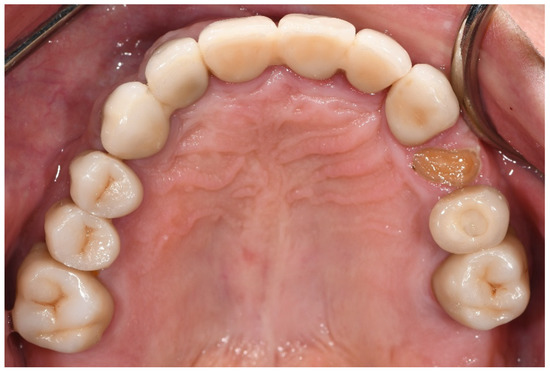

The CDA ratings were divided into those of the bruxer (Figure 3) and the non-bruxer (Figure 4) groups. The bruxer group had 96.7% excellent and 3.3% satisfactory surfaces (due to porcelain chipping and zirconia fracture); 35% excellent color; 87.6% excellent shape (due to three irreparable fractured teeth [0.9%] and five reparable open proximal contacts [1.5%] with another 10%, including the six open proximal contacts without food impaction, were evaluated as having a satisfactory shape); 45% marginal integrity rated as satisfactory (due to over contouring or open margins that led to two cases of secondary caries). The non-bruxer group comprised 98.4% excellent and 1.6% satisfactory surfaces (due to porcelain chipping and zirconia fracture); 45% excellent color; 90.2% excellent shape (due to seven reparable open proximal contacts [2.3%] with another 7.5%, including the six open proximal contacts, without food impaction, evaluated as having a satisfactory shape); and 40% marginal integrity rated as satisfactory (due to over contouring or open margins that led to three cases of secondary caries). Overall, 97.6% and 97.7% of restorations in the bruxer and the non-bruxer groups, respectively, were evaluated as satisfactory and not in need of repair or remake.

Figure 4. CDA ratings for the non-bruxer group.